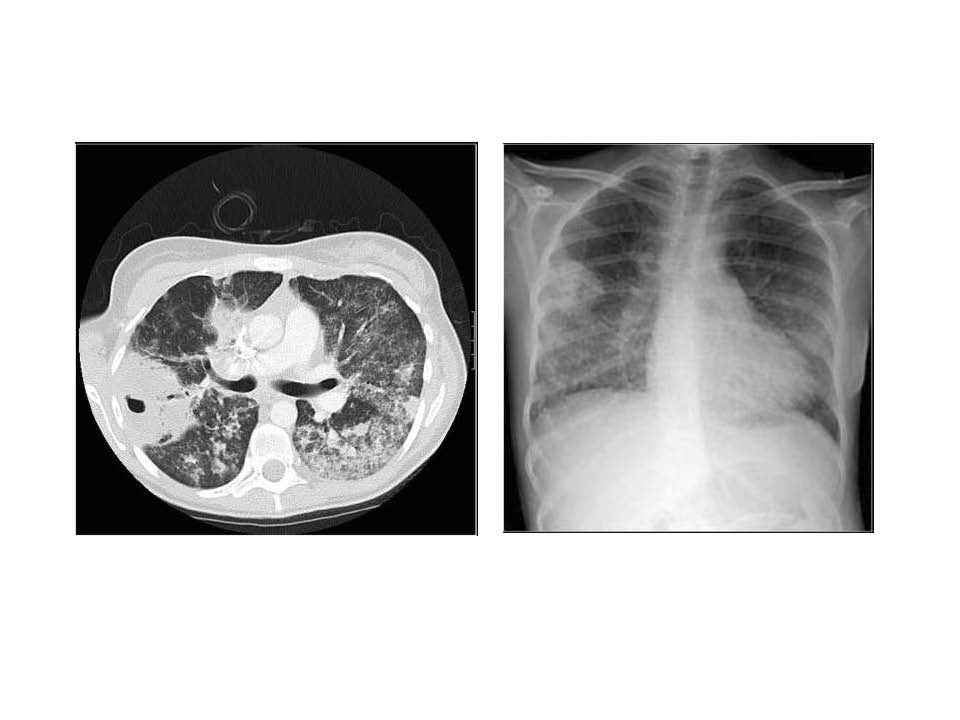

血管炎综合征 2017 Fast Facts on Vasculitis